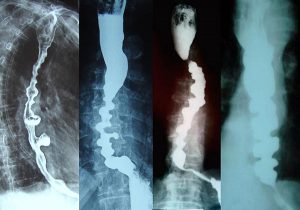

Radiografija i manometrija difuznog spazma

- Radiografija jednjaka sa barijumom – Klasični nalaz DSJ najčešće se viđa tokom barijumske radiografije, pri čemu telo jednjaka tokom simultanih kontrakcija ima izgled „vadičepa“ ili „brojanica“. Normalna peristaltika postoji u gornjoj trećini (poprečno prugasti mišići), a patološka tercijarna peristaltika se uočava u regionu donje 2/3 jednjaka (glatki mišići jednjaka). Talas kontrakcija se prostire proksimalno od nivoa luka aorte, a tercijarne kontrakcije su uglavnom visokih amplituda, dužine trajanja i učestalosti, uz povremeno postojanje pseudodivertikuluma.

- Manometrija – „zlatni standard“ u dijagnostici DSJ. Klasične abnormalnosti viđene tokom ezofagealne manometrije su nalazi simultanih kontrakcija tela jednjaka visokih amplituda. Za pouzdanu dijagnozu je neophodno prisustvo simultanih kontrakcija u više od 20% gutljaja prilikom manometrijskog pregleda. Manometrijski nalaz može ukazati i na česte, ponavljajuće kontrakcije visokih amplituda, dugotrajnije kontrakcije (> 6 sec.), talase visokih amplituda (> 180 mmHg), spontane kontrakcije nepovezane sa gutljajem. Pojedini bolesnici sa DSJ mogu imati i povišen pritisak DES-a sa neadekvatnom relaksacijom.